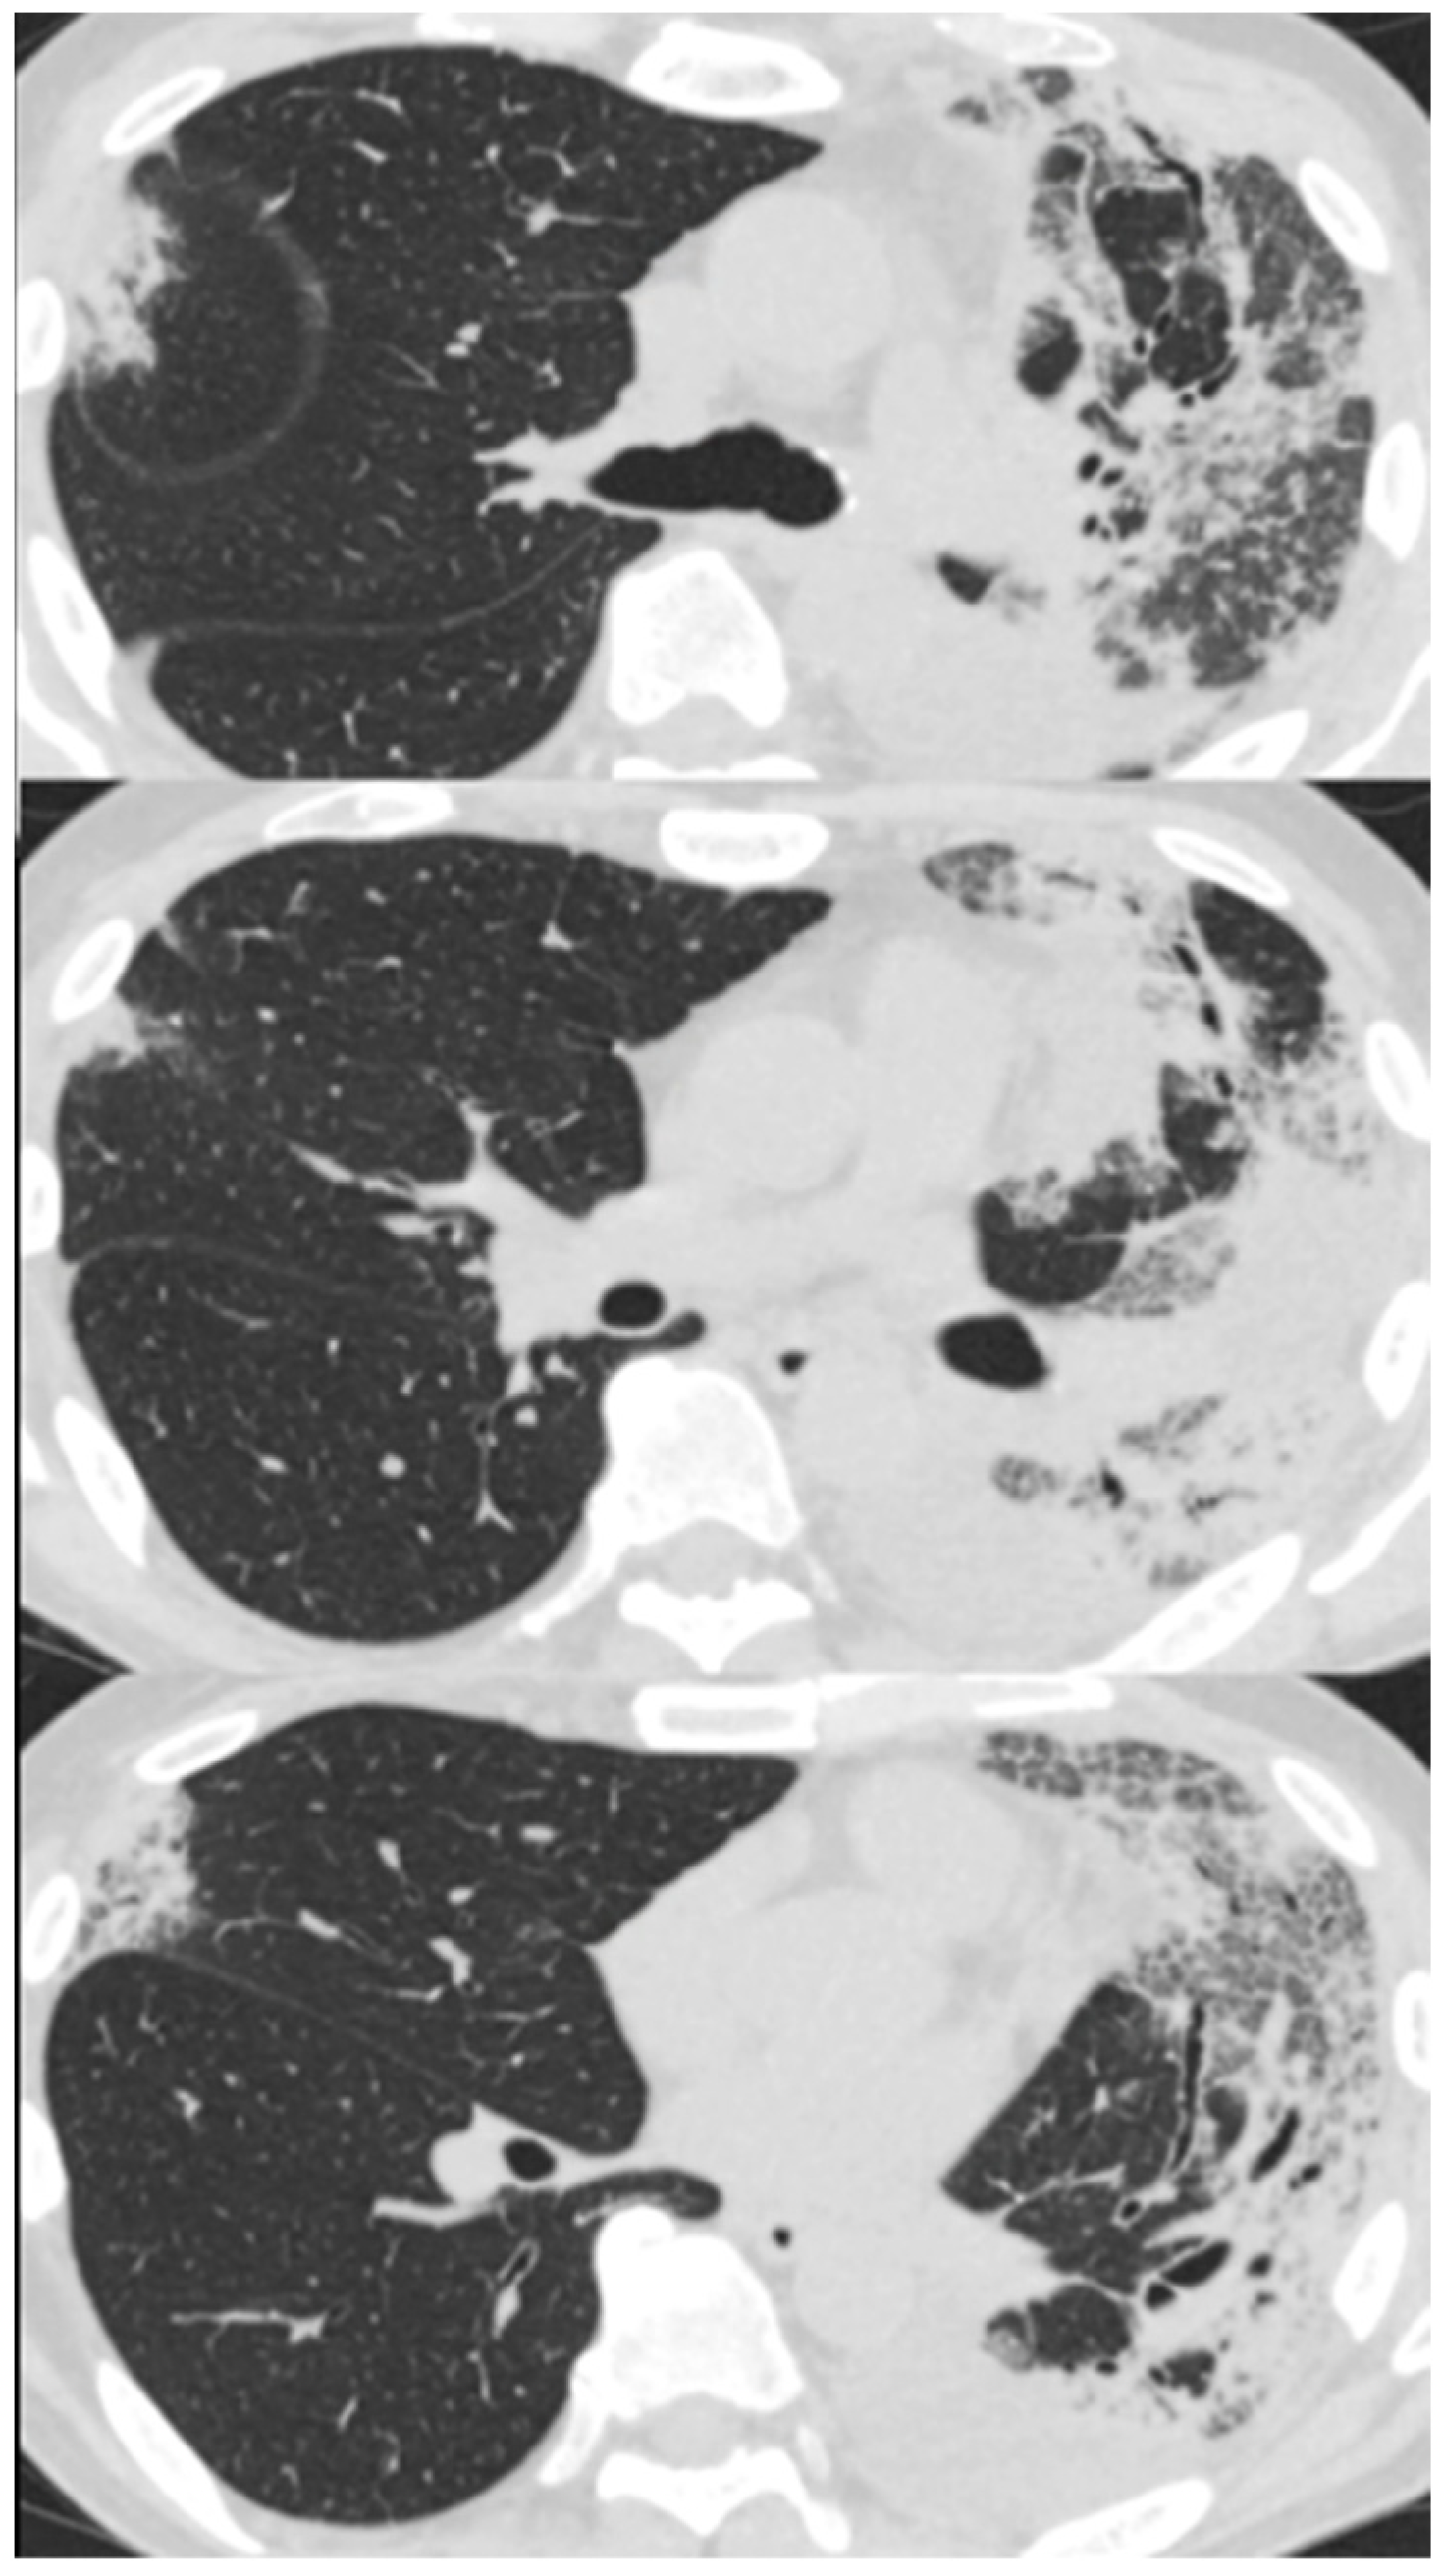

Her chest X-ray on admission showed consolidation in the bilateral peripheral-based upper lung fields and a typical radiographic pattern, i.e., “photographic negative of pulmonary edema” [3]. (Figure 1) Chest computed tomography (CT) revealed extensive ground-glass opacities in the left lung with contractile changes. Non-regional consolidation was scattered throughout the peripheral upper and middle lobes of the right lung (Figure 2).

Figure 1. Chest X-ray of 55-year-old woman upon admission with fever and dyspnea. It showed bilateral consolidation in her upper lung fields.